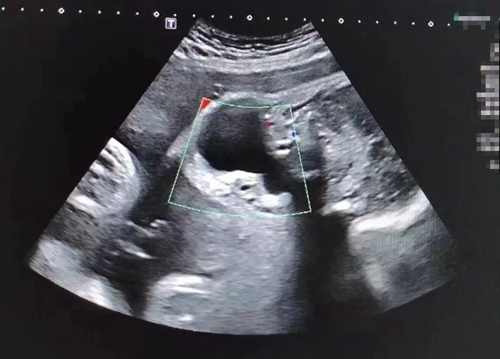

胎兒醫(yī)學(xué)門診接診專家通過超聲發(fā)現(xiàn)胎兒頸部有一個(gè)11*6mm約蠶豆大小的囊性包塊,專家推測(cè)包塊為淋巴管瘤或鰓源性囊腫,要先進(jìn)行羊水穿刺排除胎兒染色體異常導(dǎo)致的智力低下和生長發(fā)育等先天性疾病,再根據(jù)孕期囊腫情況制定治療方案。孕20周,忐忑又緊張的夫妻倆再次來到青島婦女兒童醫(yī)院進(jìn)行羊水穿刺,檢查結(jié)果提示:染色體未見明顯異常。一般來說,排除了遺傳學(xué)和其他結(jié)構(gòu)異常的頸部囊腫絕大多數(shù)預(yù)后良好,這也堅(jiān)定了夫妻倆想要留住寶寶的決心。

隨著孕周增加,胎兒頸部包塊逐漸增大。孕39周時(shí),超聲提示囊腫增大至42*39.9mm,為確保母嬰安全,胎兒醫(yī)學(xué)中心、產(chǎn)科專家經(jīng)過分析決定為孕婦實(shí)行剖宮產(chǎn)。醫(yī)護(hù)團(tuán)隊(duì)反復(fù)評(píng)估和討論,制定了周密的手術(shù)計(jì)劃,芳芳順利分娩一名女嬰。寶寶出生后,專家檢查發(fā)現(xiàn)囊腫位于患兒咽后及左側(cè)動(dòng)脈間隙,可能流膿、感染,且腫物越長越大,可能壓迫寶寶氣管,手術(shù)風(fēng)險(xiǎn)和麻醉風(fēng)險(xiǎn)都將進(jìn)一步提升,必須及早手術(shù)。